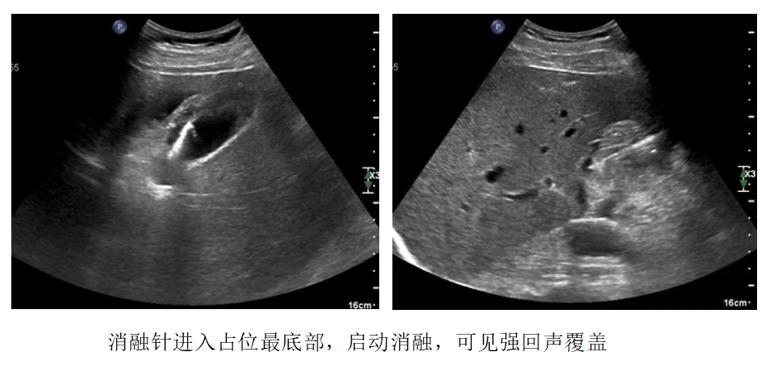

水隔离—注射生理盐水,使胆囊壁浆膜层和黏膜层分离完全,形成厚度>10mm的“隔离带”,使胆囊壁形成显著水肿,增加进针的安全距离。此操作在完成穿刺活检及射频消融中起了决定性的作用!

穿刺—选择最佳穿刺点及进针角度,沿胆囊壁长轴方向进针,尽可能增加路径距离,减小损伤胆囊壁穿孔、造成胆漏的风险。

活检完成,开始射频消融: